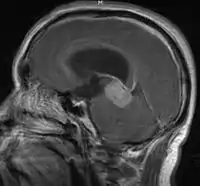

- Mainly located in midline structures, suprasellar region or pineal gland, also basal ganglia and hypothalamus

- Pineal Gland Germinoma